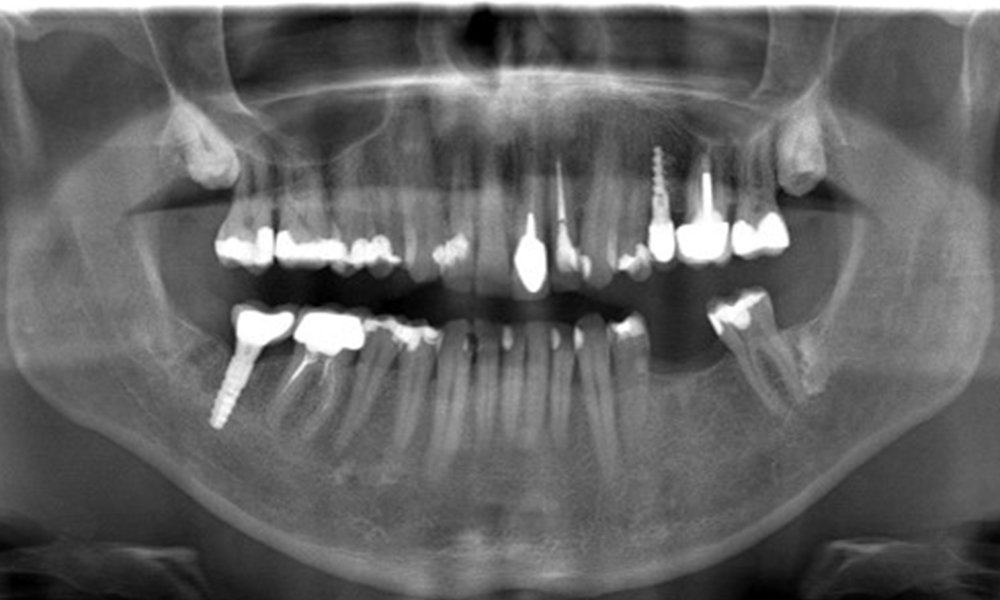

The X-ray image shows the bone loss

The X-ray images show the bone loss.

OPG: 29/02/2024

X-ray images (or bitewing X-rays)

X-ray images (or bitewing X-rays) taken on: 18/02/2021